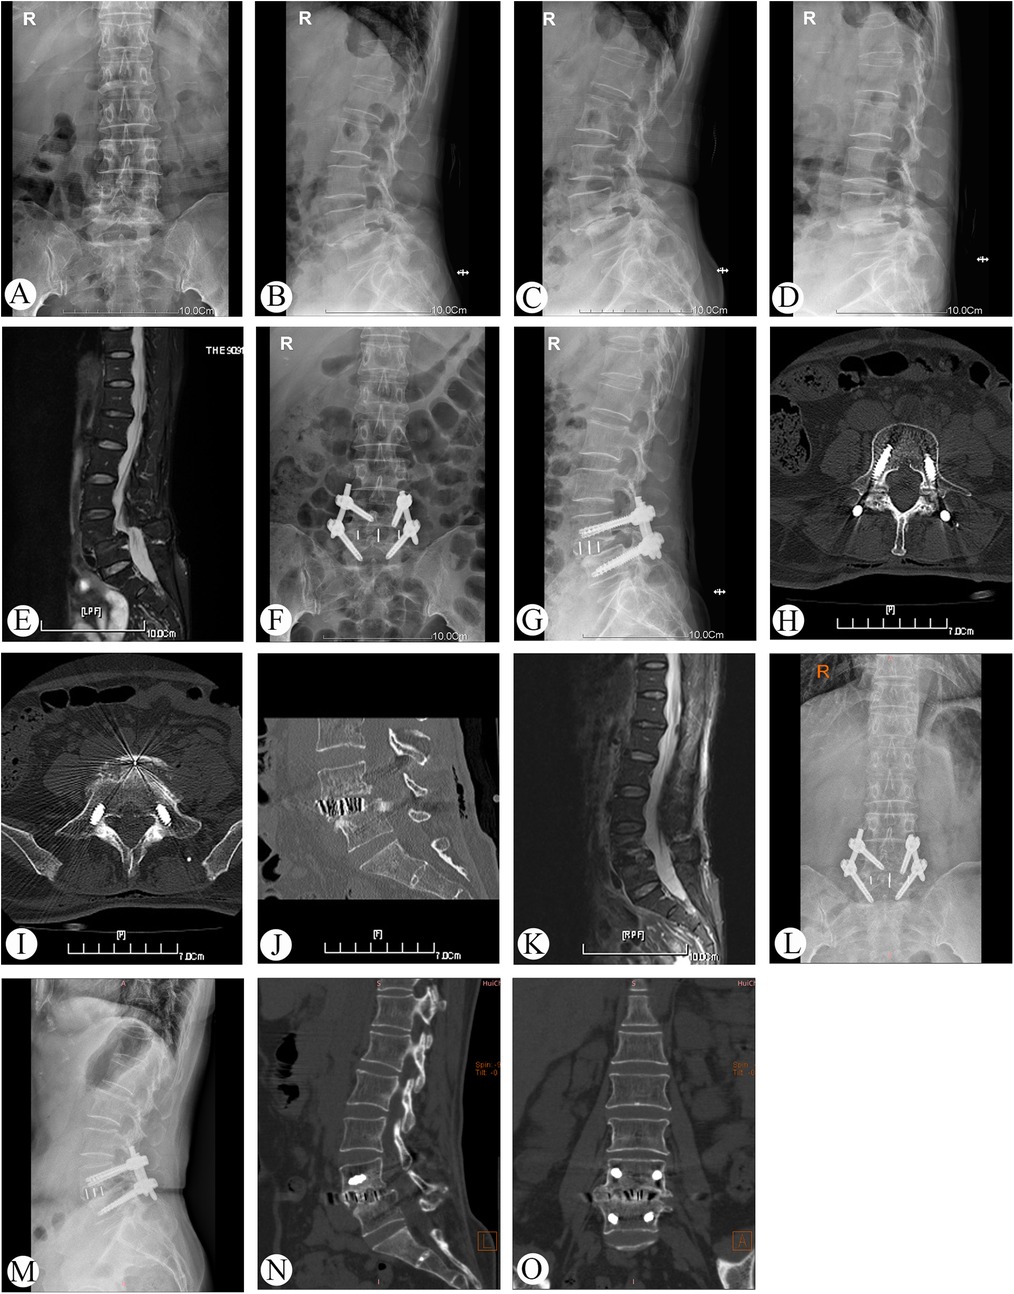

Single-Position OLIF Combined with Percutaneous Posterior Fixation Under O-Arm Navigation for the Treatment of Grade II Lumbar Spondylolisthesis: Clinical and Radiologic Outcomes

Introduction and aim: Grade II lumbar spondylolisthesis is frequently accompanied by segmental instability, intervertebral disc degeneration, and nerve root compression. When conservative management fails, surgery is generally warranted. Therefore, we conducted a retrospective study to evaluate the clinical and radiologic outcomes of single-position OLIF combined with percutaneous posterior fixation under O-arm navigation for the treatment of Grade II lumbar spondylolisthesis. Materials and methods: A retrospective analysis was conducted on 87 patients with Grade II lumbar spondylolisthesis who underwent single-position OLIF combined with percutaneous posterior fixation under O-arm navigation. The affected segments were as follows: 17 cases at L2, 26 cases at L3, and 44 cases at L4. Data were collected on operation duration, blood loss, hospital stay, radiological and clinical outcomes (VAS, ODI, SF-36, intervertebral disc height, slippage rate, lumbar lordosis angle, cross-sectional area, and sagittal diameter), Bridwell classification, and complications. Results: The mean operation duration was 118.7 ± 22.4 min, with an average blood loss of 83.6 ± 27.4 mL. All patients had regular follow up with an average duration of 29.5 ± 9.2 months. The VAS scores, ODI, and SF-36 at 3 months postoperatively and final follow-up showed significant improvement compared to preoperative scores (P<0.05). The IDH, SR, and LLA were significantly improved at 3 days, 12 months, and at the final follow-up compared to preoperative values (All P<0.01). Mean cross-sectional area improved significantly from 87.40 ± 29.59 mm2 preoperatively to 132.42 ± 33.53 mm2 at 12 months follow-up (P<0.001). The mean sagittal diameter at 12 months follow-up 9.23 ± 2.87 mm showed statistically significant difference compared to preoperative measurements 5.25±2.67 mm. 94.3% (82/87) of patients achieving Bridwell Grade I bone fusion. A total of 348 pedicle screws were implanted with an overall accuracy rate of approximately 98.9%. Complications were minimal, with 3 cases of psoas weakness that resolved to normal muscle strength within 2 weeks. Conclusions: It offers significant minimal invasiveness, accuracy in screw placement, and sustained reconstruction of lumbar sagittal plane, with low complication rates and high fusion success.